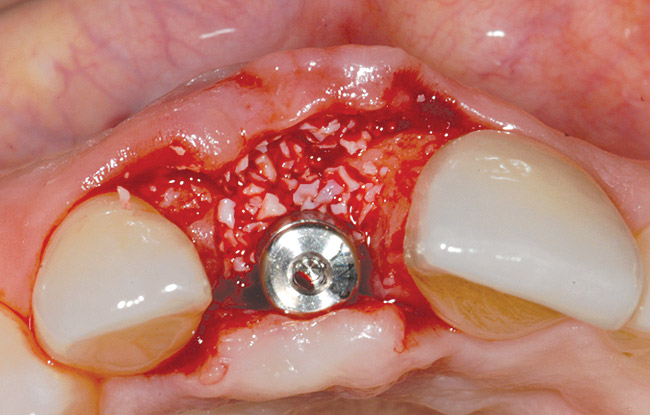

A 39-year-old woman presented with a failing endodontically treated maxillary right central incisor. Clinical and radiographic examination revealed a thick, flat periodontal biotype, high smile line, and a fistulous tract of the labial vestibule opposite the incisor (Figure 16 and Figure 17). Also noted post-extraction was a thin (< 2 mm) labial plate with 8 mm of vertical bone loss (Figure 18). Treatment consisted of a conservative flapless extraction with placement of a free connective tissue graft (Figure 19) sutured through the socket, along with placement of a bone mineralized allograft (MinerOss) (Figure 20 and Figure 21). Five months post-extraction, a root-form implant was placed, nonsubmerged, along with a bovine bone xenograft as a veneer into a sub-periosteal labial pouch (Figure 22 through Figure 24). A provisional crown was placed 3 months later, allowing for adequate soft-tissue grooming (Figure 25).

Figure 22  A thin labial plate (< 2 mm) at Stage I surgery.

Figure 22

Figure 23  Labial plate veneer graft with bovine hydroxyapatite.

Figure 23

Figure 24  Positive labial plate contour, 3 months after graft placement.

Figure 24